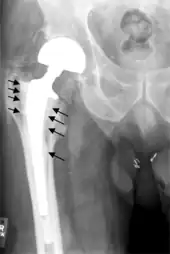

Intraoperative fractures may occur. After surgery, bones with internal fixation devices in situ are at risk of periprosthetic fractures at the end of the implant, an area of relative mechanical stress. Post-operative femoral fractures are graded by the Vancouver classification.